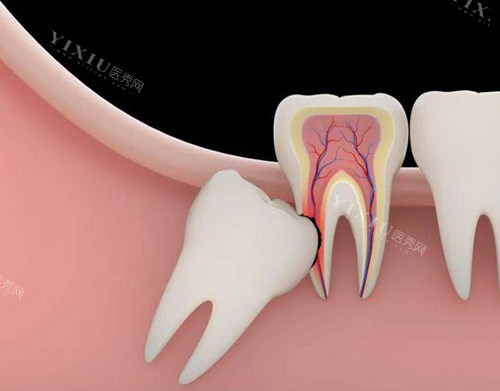

水平阻生智齿:1200元起(完全横卧,需去骨操作)

完全埋伏智齿:1500元起(未萌出,需影像引导及小创口手术)

骨埋伏+多生牙拔除:2000-2500元起(涉及复杂解剖结构)